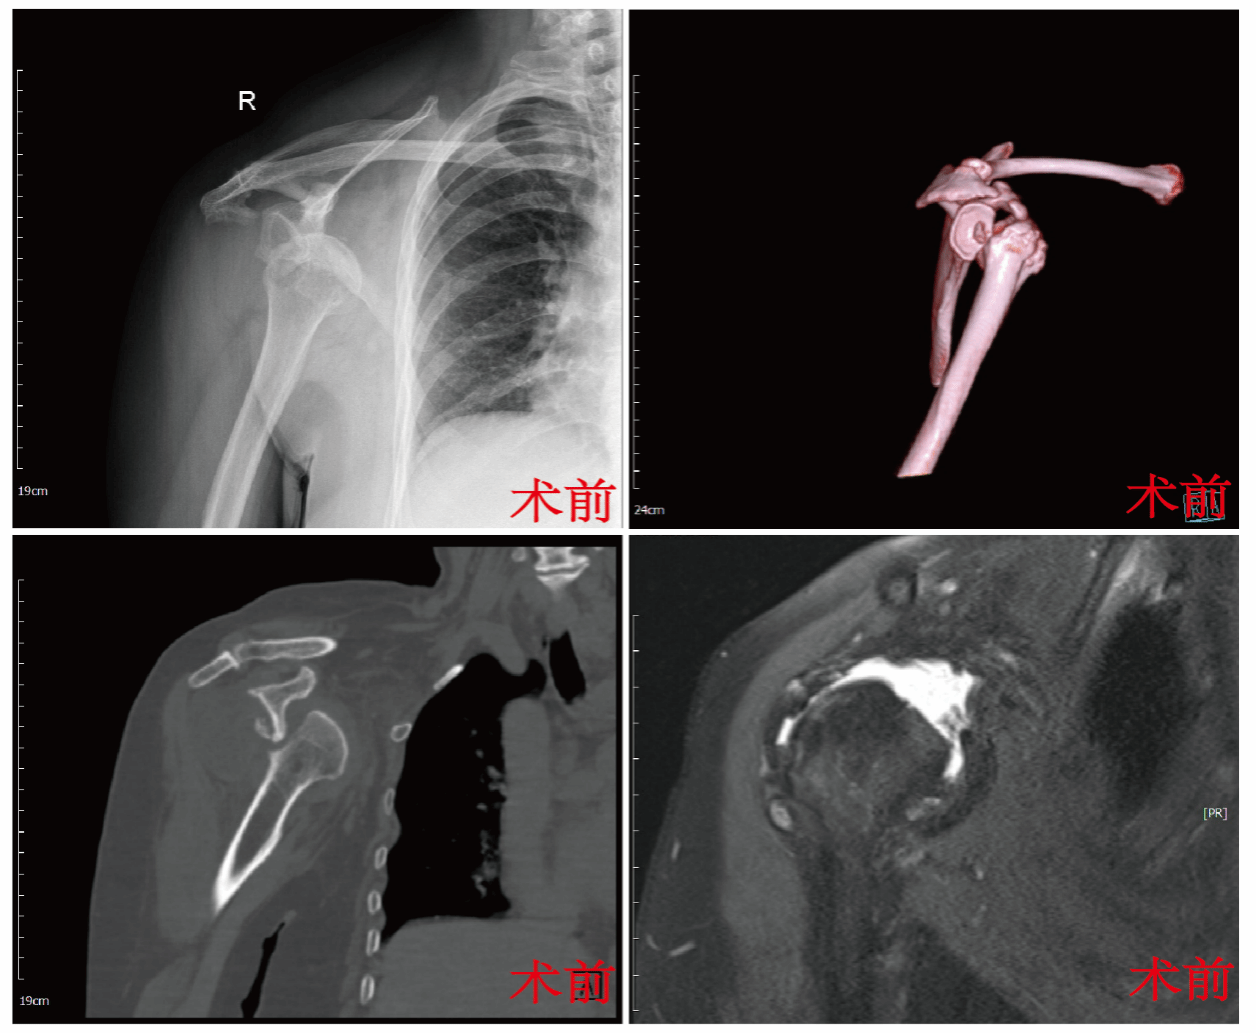

经过进一步检查,张晨副主任发现寇阿姨肩关节损伤严重,冈上肌与肩胛下肌的巨大撕裂导致关节稳定性丧失,同时肩关节盂前方存在超过25%的骨缺损,传统修复方法难以有效解决。

面对复杂病情,为了兼顾治疗、安全与术后恢复,科室组织全科术前讨论,由科室主任杨佩主任医师主持,中华医学会骨科学分会主任委员王坤正教授指导,潘韩丽护士长亦带领专科护理团队参与。经专家指导及团队深入讨论,结合寇阿姨个体情况,最终确定了代表国际前沿理念的个体化治疗方案:在肩关节镜下实施肩袖修补术,同期联合Latarjet手术(喙突截骨移位骨块固定术)。张晨谈到,该方案通过微创技术,一次性修复软组织撕裂并重建骨性结构,为肩关节构建稳固的支撑,能够显著提升治疗效果。

手术当日,张晨带领团队为寇阿姨实施手术,术中在高清关节镜引导下,精准锚定缝合撕裂的冈上肌与肩胛下肌,重建肩袖完整性;随后巧妙截取自体喙突骨块,精确移植固定于肩胛盂严重骨缺损处,恢复关节盂正常弧度与稳定平台;最后精细调整联合肌腱位置,为关节提供动态稳定力。手术过程顺利,目前,患者身体逐渐恢复。